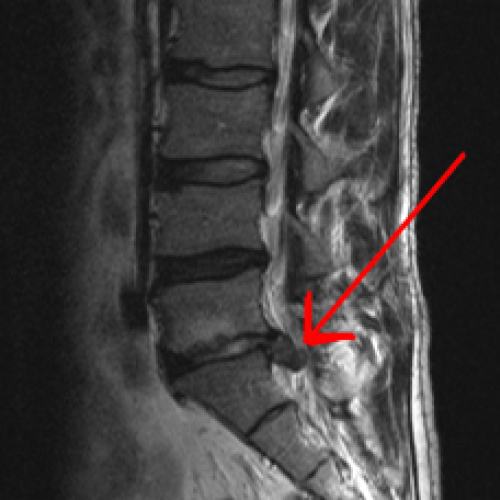

Αποτελεί μια από τις συχνότερες αιτίες χαμηλής οσφυαλγίας με συνοδό ισχιαλγία και ριζιτική συνδρομή (άλγος και μούδιασμα κάτω άκρου).

Από το ιστορικό του ασθενούς η εμφάνιση της οσφυαλγίας μπορεί να είναι είτε με οξύ άλγος κατά την άρση βάρους ή οσφυαλγία λόγω καταπόνησης της σπονδυλικής στήλης κατά την καθημερινότητα (καθιστική εργασία).

Η διάγνωση γίνεται μέσω της κλινικής εξέτασης με τις διάφορες κλινικές δοκιμασίες που υποβάλλει ο ορθοπεδικός τον ασθενή ενώ η επιβεβαίωση καθώς και η σοβαρότητα - μέγεθος της κήλης γίνεται με τη διενέργεια μαγνητικής τομογραφίας της σπονδυλικής στήλης.